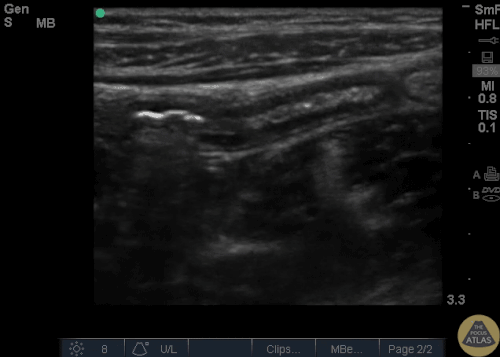

Những hình ảnh trắng đen, có màu và chú thích giải phẫu bình thường vị trí ¼ dưới phải vùng bụng

Ap = Appendix (ruột thừa) , P = Psoas, Ia = Iliac Artery (động mạch chậu), Iv = Iliac Vein (tĩnh mạch chậu)

Mặt cắt dọc